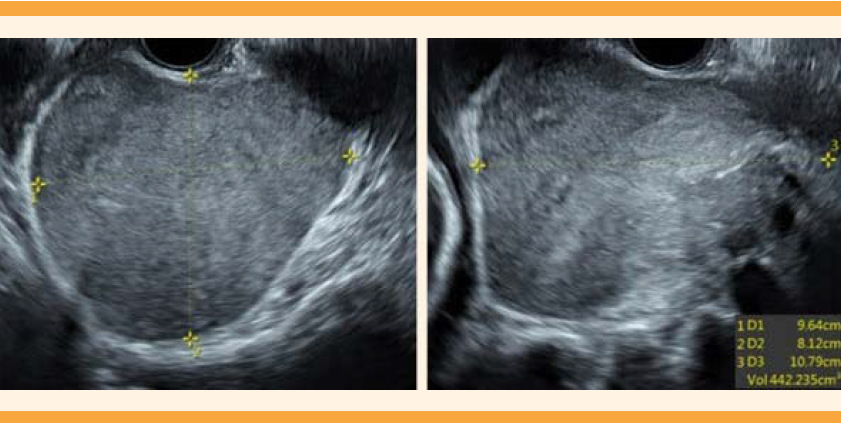

Paciente de 32 años, primigesta, con 16 semanas de embarazo. Acudió a Urgencias debido a un dolor en el hipocondrio derecho, tipo cólico, de intensidad 6 de 10, de 15 días de evolución. En los controles prenatales previos no se habían reportado complicaciones. Las cifras tensionales al ingreso fueron: 120-76 mmHg, frecuencia cardiaca de 75 lpm, frecuencia respiratoria de 18 rpm, temperatura de 36.9 oC. Dolor a la palpación en la parte derecha del hipocondrio, sin signos de irritación peritoneal, con una altura uterina de 15 centímetros, frecuencia cardiaca fetal de 143 lpm. Sospecha diagnóstica: cólico biliar, causa del dolor abdominal. Se decidió hospitalizarla para efectuarle estudios complementarios, y controlar el dolor. El hemograma no reportó leucocitosis ni neutrofilia. Las pruebas de función hepática reportaron que las concentraciones de transaminasas eran normales, lo mismo que de bilirrubinas. La ecografía obstétrica informó adecuado bienestar fetal. La ecografía total del abdomen evidenció colelitiasis y una masa en el fondo de saco de Douglas retroperitoneal, con contornos regulares, hipoecogénica, sólida, de 107 x 96 x 81 milímetros, con captación Doppler central tipo II (Figura 1). La resonancia magnética confirmó la existencia de una masa sólida, de contornos parcialmente definidos, localizada en el espacio presacro, de 100 x 85 x 90 milímetros; hipointensa en T1 e hiperintensa en T2. La masa contenía conductos hipointensos en T2 que se extendían a los forámenes sacros derechos. En las estructuras óseas y vasculares no se identificaron alteraciones (Figura 2). La impresión diagnóstica fue de tumor retroperitoneal, de origen neural. Ante el diagnóstico de tumor de naturaleza desconocida se solicitó el estudio de los marcadores tumorales: CA-125: 39.7 U/mL, antígeno carcinoembrionario: 0.4 ng/mL, antígeno carbohidratado: 19-9 (CA 19-9): 9.35. U/mL. La biopsia percutánea, guiada por tomografía, se informó sin complicaciones (Figura 3). Al segundo día de hospitalización desapareció el cólico biliar, razón para otorgarle el alta hospitalaria.

Figura 1 Ecografía del ganglioneuroma: lesión sólida, de contornos regulares, hipoecogénica, homogénea de 107 x 96 x 81 milímetros.